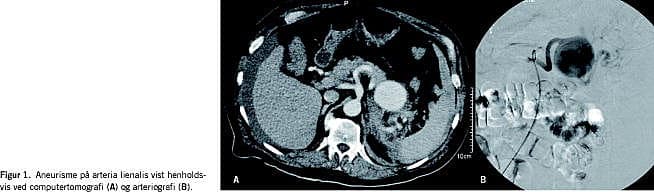

Under den seneste indlæggelse blev AMI afkræftet og en bed side-ekkokardiografi viste normal pumpefunktion. Patientens blodtryk faldt i løbet af de næste par døgn til 59/35 mmHg, og han var på et tidspunkt pulsløs i 30 s, men fik spontan sinusrytme igen. Der blev i løbet af to dage observeret et fald i hæmoglobin fra 7,9 mmol/l til 4,9 mmol/l, og blodtransfusioner blev påbegyndt. Smerterne persisterede, hvorfor der blev udført CT, der viste et 5,6 cm stort aneurisme på arteria lienalis og tillige blødning omkring aneurismet, pancreas og leveren (Figur 1A). Ved gennemgang af CT fra to år tidligere kunne man se samme aneurisme, der da målte 4 cm i diameter.

Patienten blev efter CT'en overflyttet til Odense Universitetshospital mhp. behandling. Da der var mistanke om ruptur valgte man at foretage endovaskulær embolisering af a. lienalis. Igennem sheath i a. femoralis blev et emboliseringskateter ved hjælp af røntgenkontrast og gennemlysning fremført via aorta og truncus coeliacus til a. lienalis (Figur 1B). Med spidsen af kateteret beliggende i aneurismesækken blev der udløst coils, og disse flød med blodstrømmen til afgangsarterien og emboliserede denne. Herefter blev kateteret retraheret, og tilgangsarterien blev ligeledes emboliseret med coils. På den måde blev aneurismet totalt ekskluderet. Efter indgrebet var patienten velbefindende og kunne tilbageflyttes til stamsygehuset den følgende dag.